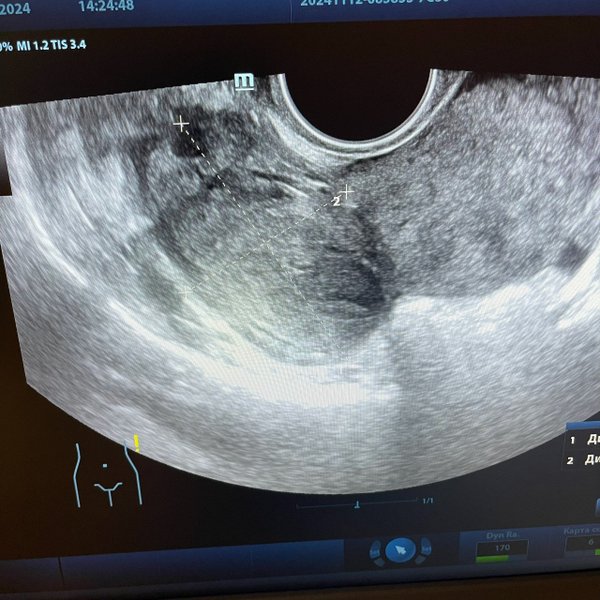

Бородулина Наталья (Врач УЗИ, Косметология) (05.12.2024): #беременность малого срока (продолжение..) ⠀ Что будет сначала видно на #узи осмотре Кто ходил в ранних сроках на узи знает, что эмбрион виден не сразу. Сначала видно плодное яйцо, потом появляется желточный мешочек, и последним появляется эмбрион. ⠀ Плодное яйцо в матке начинает достоверно визуализироваться при размере от 4 мм. ⠀ ️С какой скоростью должно расти плодное яйцо в норме? 0,8—1,2 мм/сут ⠀ ️Когда появляется сердцебиение у эмбриона? При размере его 5—7 мм! ⠀ ️Когда дол… — Читать дальше

жен появиться эмбрион в плодном яйце? При диаметре плодного яйца 16—24 мм Вот такие дела

Бородулина Наталья (Врач УЗИ, Косметология) (04.12.2024): Вы сделали тест на беременность и он показал // две полоски! ‼️ Но не спешите бежать на узи. Вы должны понимать, что плодное яйцо на #узи мы увидим не ранее, чем через 5—7, а часто и 10 дней задержки! ⠀ Почему же тест положительный, а на узи не видно? ⠀Потому, что тест улавливает ХГЧ (гормон #беременных) практически через 3 дня после имплантации (внедрении) плодного яйца в полость матки (в теории это 9—10 день после овуляции и 24 день цикла). Т.е. ещё даже до задержки. Это я рассмотре… — Читать дальше

ла цикл 28 дней. И конечно же, если цикл более длинный, #овуляция позже и тогда день овуляции, а следовательно и имплантации смещается.